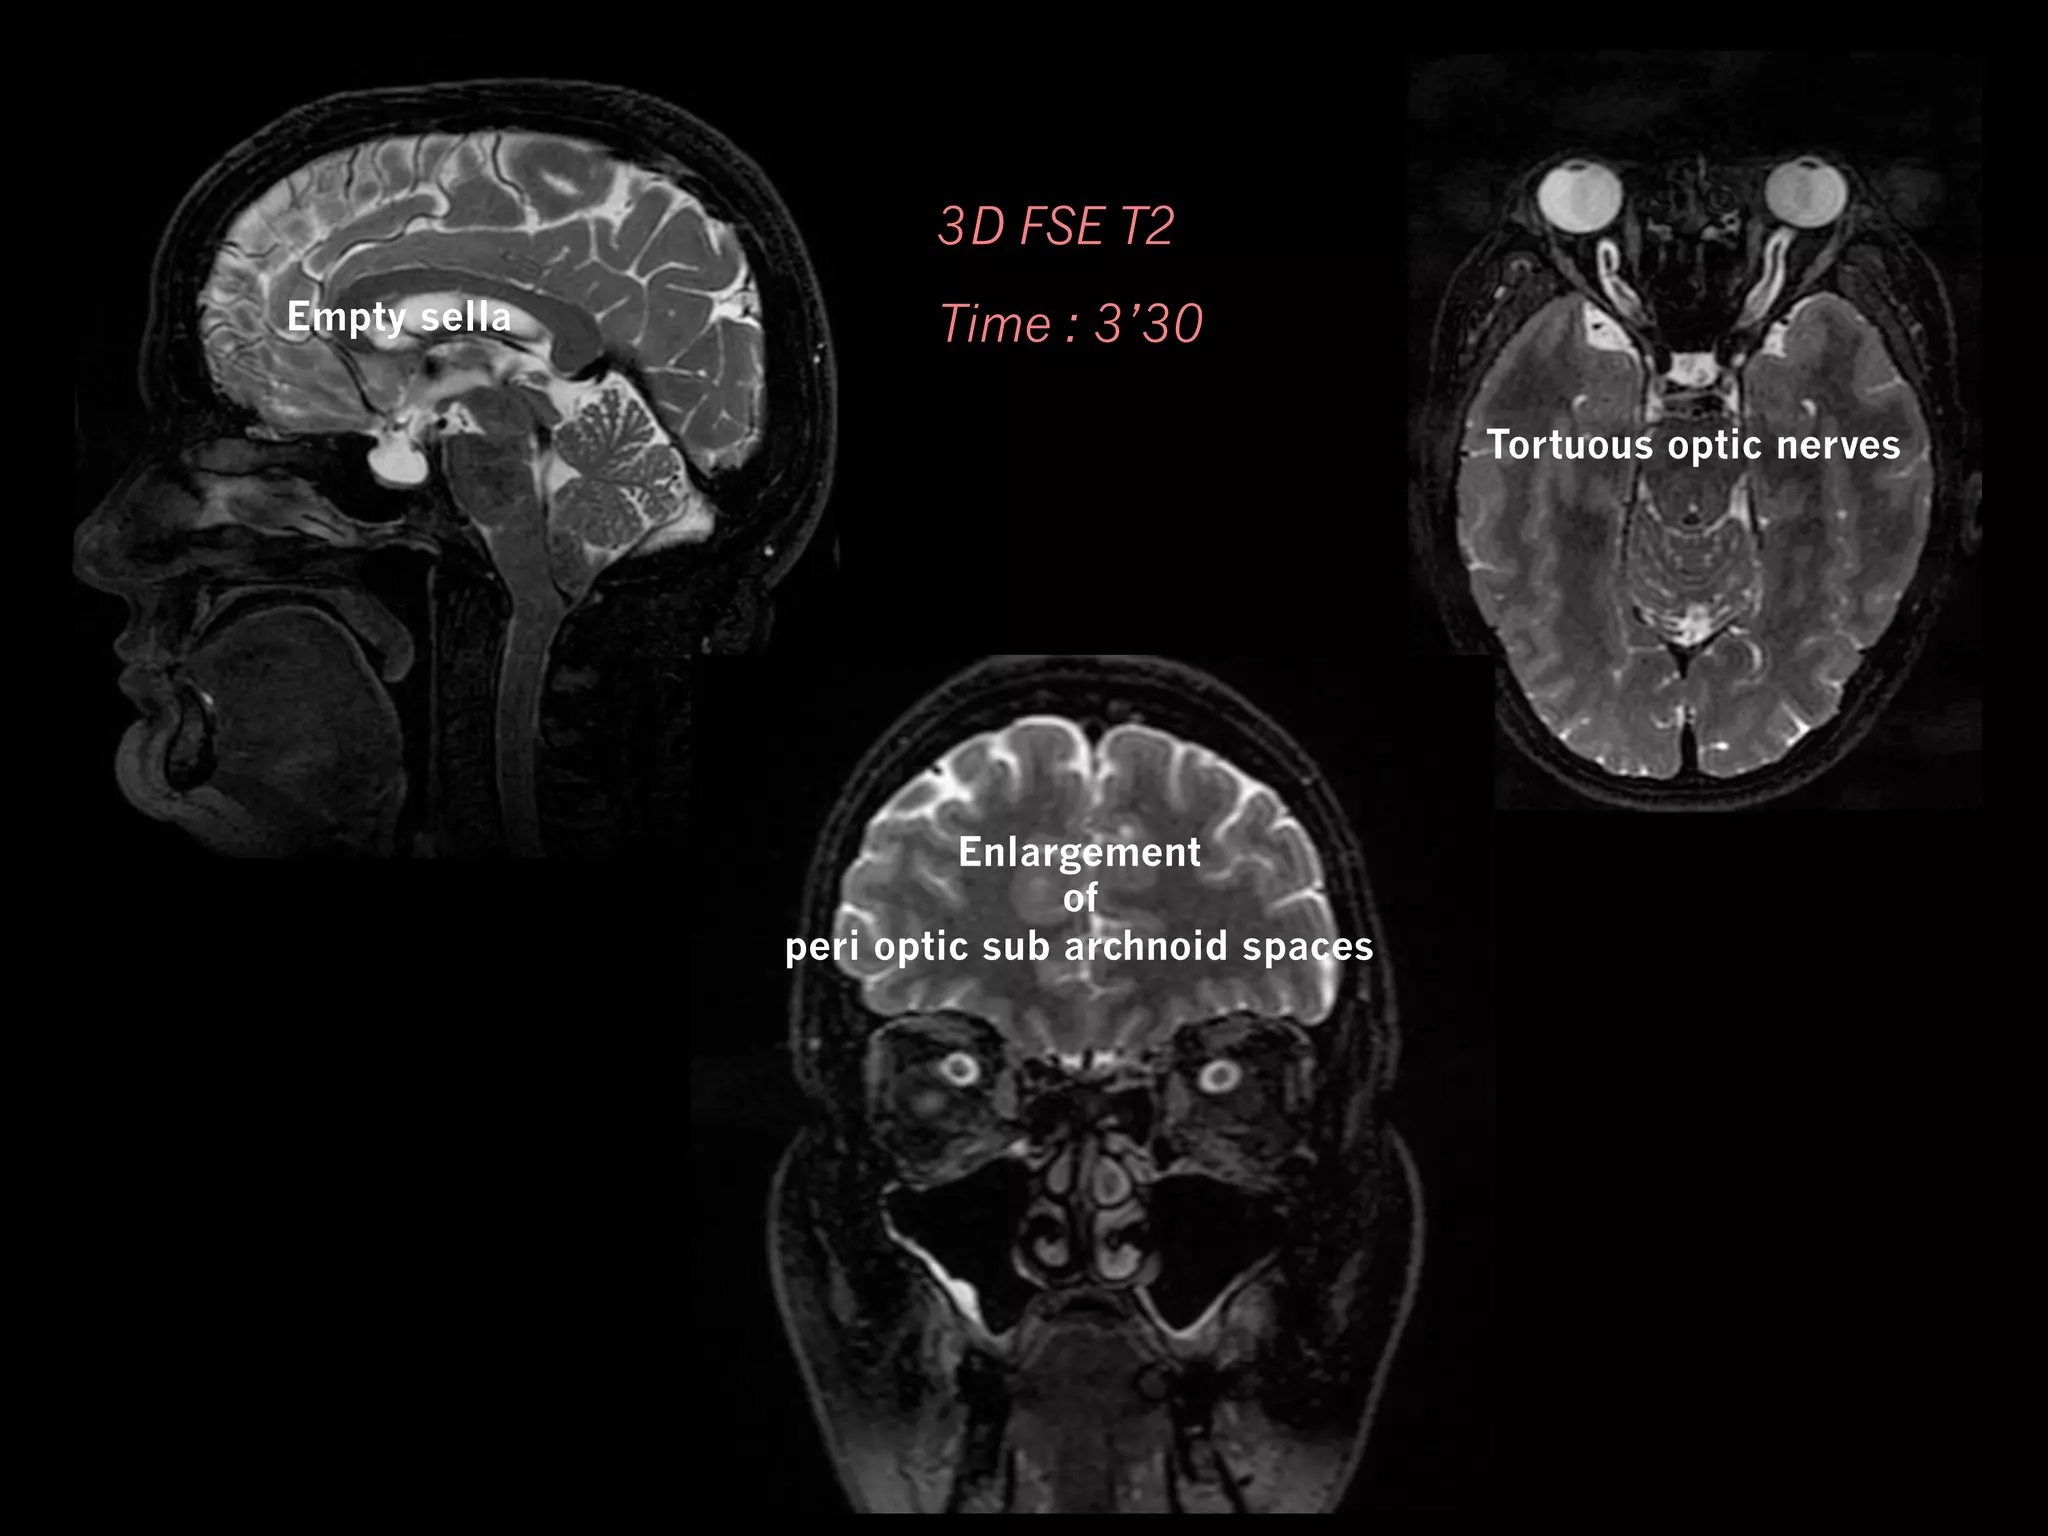

3D FSE T2

Empty sella

Time : 3’30

Tortuous optic nerves

Enlargement

of

peri optic sub archnoid spaces

MRI Axial (or frontal)T2w : orbital exploration +++ —  Tortuous optic nerves (> 7O%) —  Enlargement of peri optic subarachnoid space (70%) —  Flattening of posterior globe (45%)

• 51.

3D FSE T2 Emptysella Time : 3’30 Tortuous optic nerves Enlargement of peri optic sub archnoid spaces